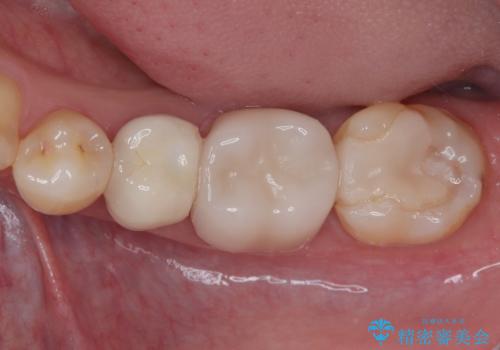

- 左右ともに下顎の奥歯に違和感や痛みを感じるとのことで来院された患者様です。

左下奥歯は詰め物と周辺の歯が欠けて、しみている状態でした。

部分的な詰め物ですと、再度破損リスクが高いため、高強度のセラミッククラウンにて補綴治療を行うこととしました。

また、親知らずが埋もれており、よい機会なので抜歯を行ってからセラミッククラウンを装着することとしました。